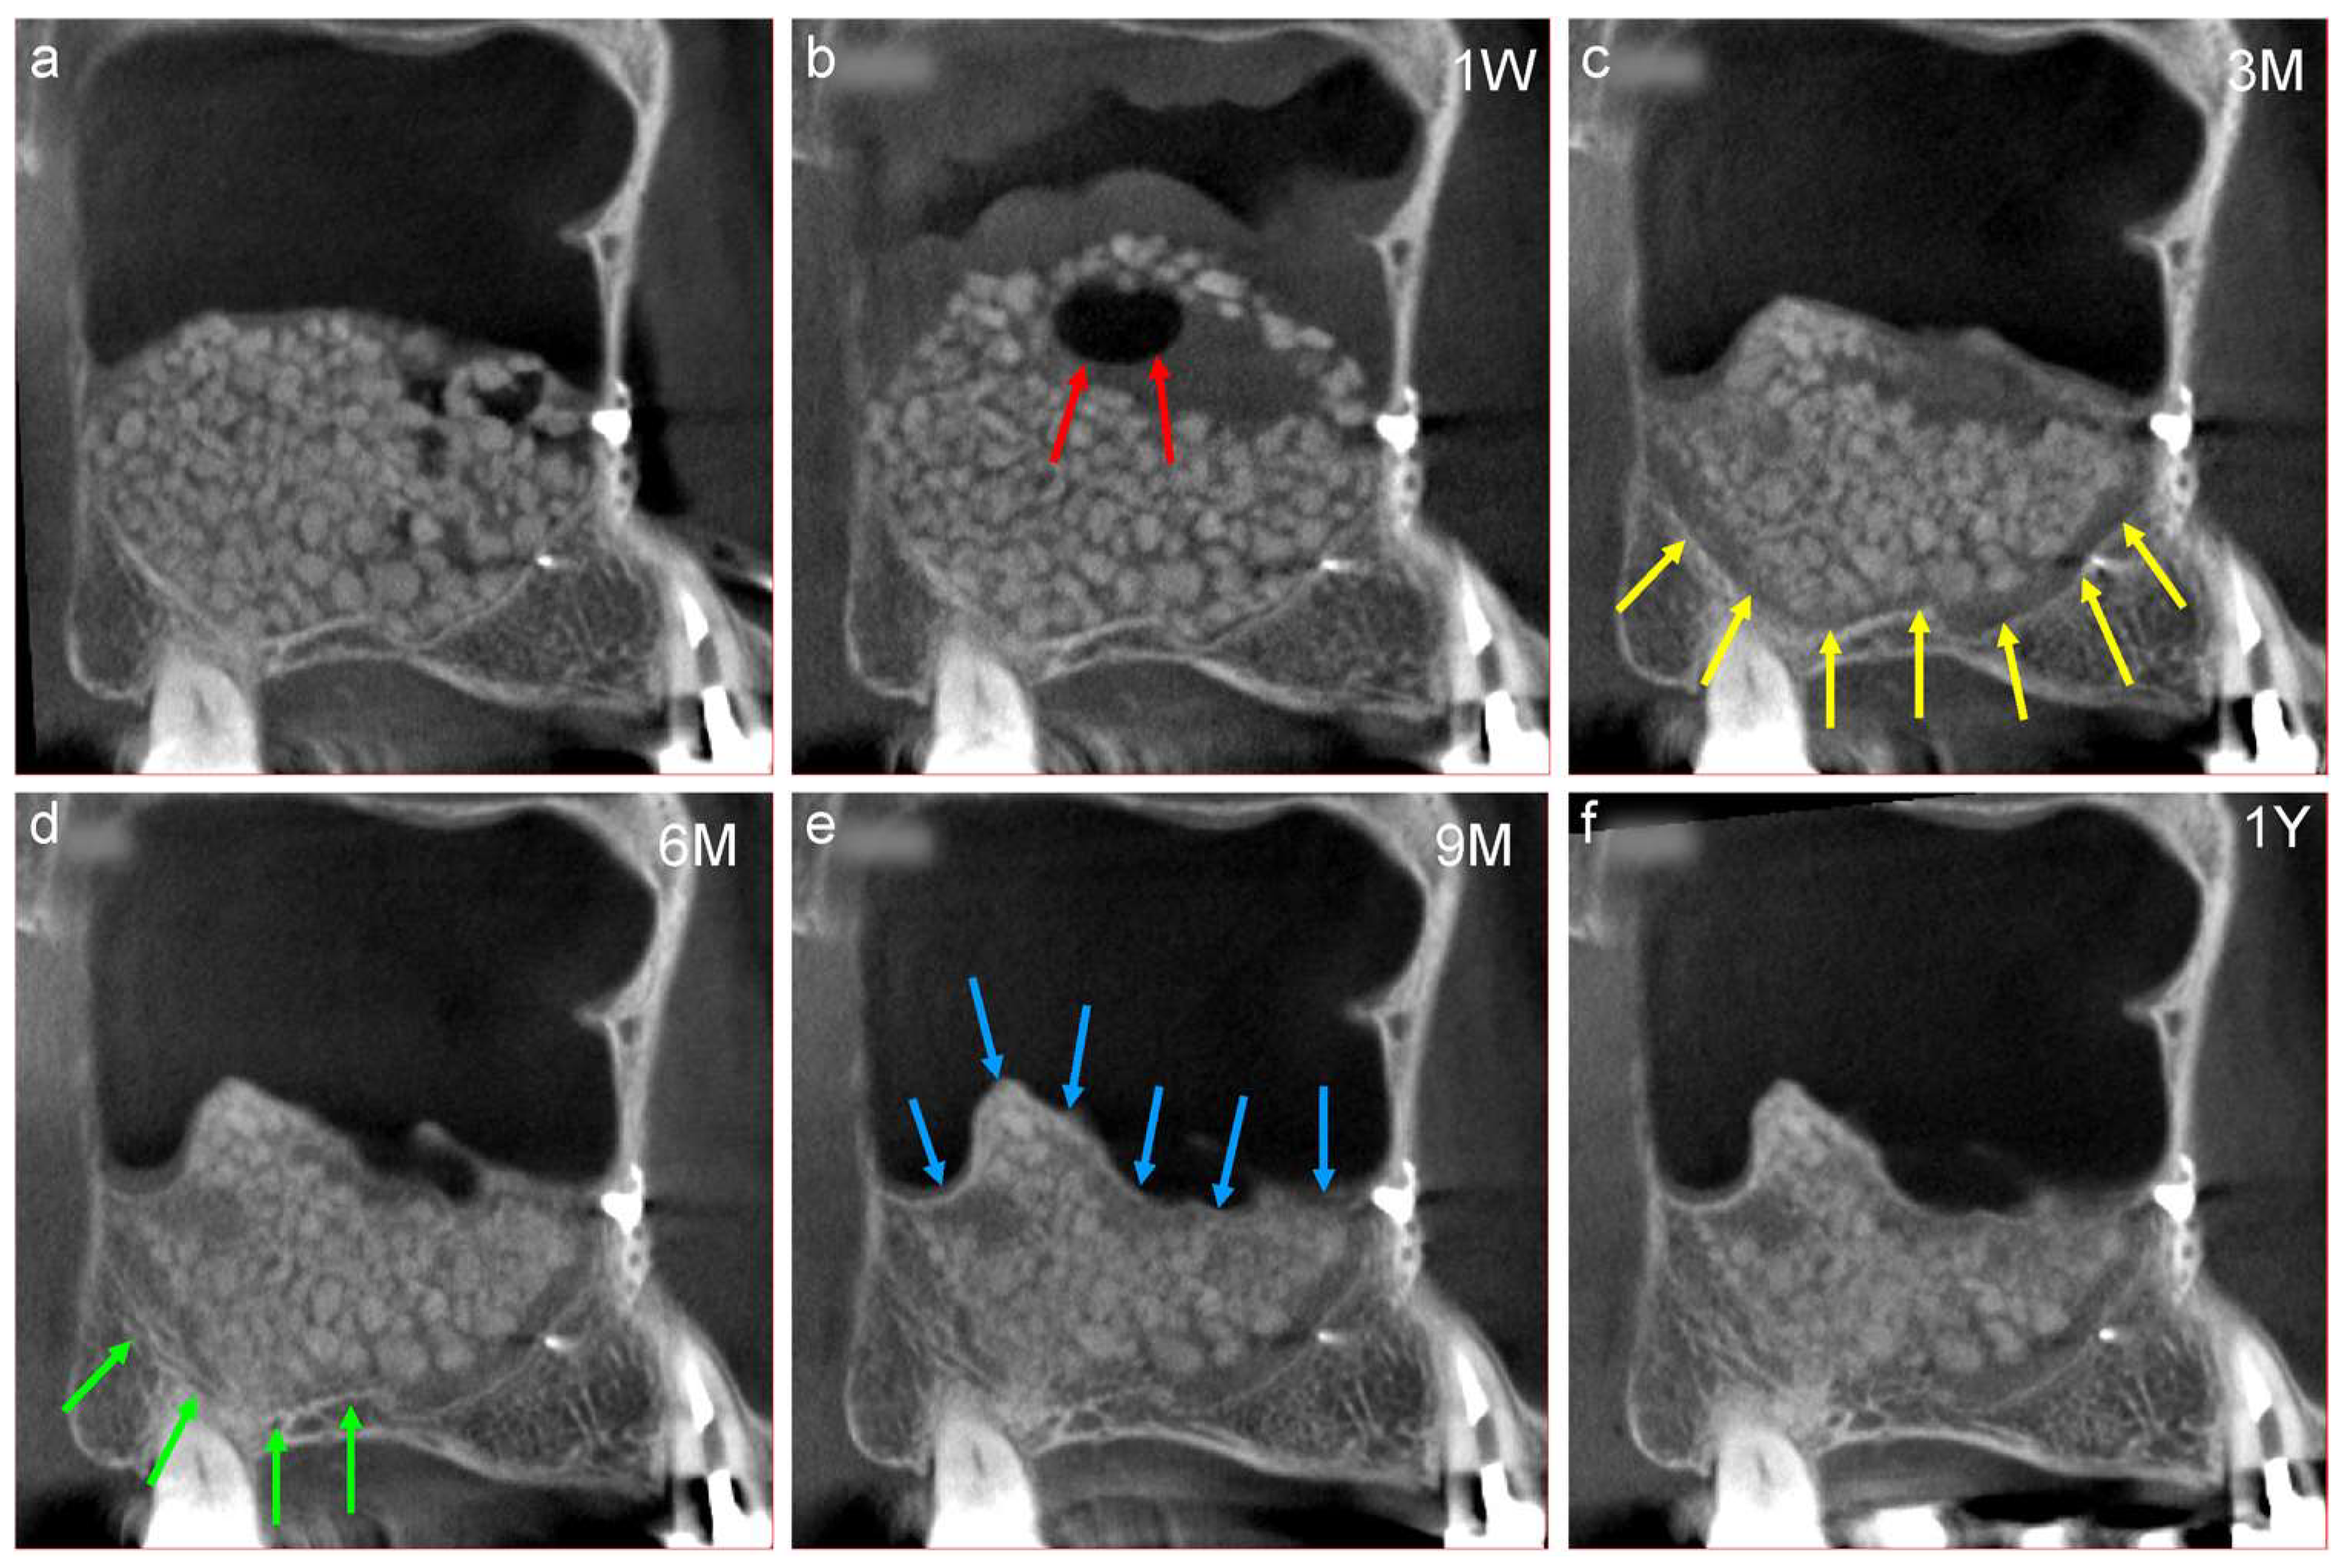

Figure 7.

(a) Mesiodistal section of the CT image obtained after sinus floor elevation. Sufficient β-TCP granules are observed at the augmented area. (b) One week after surgery, the β-TCP granules moved upward owing to postoperative swelling of the sinus membrane. An air around β-TCP granules has accumulated at the upper portion of the augmented area (red arrows). 1W; one week follow-up (c) Swelling of the sinus membrane disappeared spontaneously three months postoperatively, and a belt-shaped radiolucency (grey zone) is observed at the interface between the β-TCP granules and the surface of the maxillary sinus (yellow arrows). 3M; three months follow-up (d) The radiopacity of the original cortical bone decreased six months postoperatively, and that of the grey zone increased (green arrows). 6M; six months follow-up (e) A complete radiopaque line (white line) is observed at the newly formed bottom of the maxillary sinus (blue arrows) nine months postoperatively. 9M; nine months follow-up (f) The white line becomes clear 12 months postoperatively; however, the β-TCP granules in the central area retained their shape. 1Y; one year follow-up.

The representative chronological CT images of a 58-year-old female are described below.

- The β-TCP granules moved upward owing to postoperative swelling of the sinus membrane one week postoperatively. These movements of bone materials determine the final shape of the augmented area (Figure 7b,f). As the weight of the air surrounding the β-TCP granules is comparatively low, it accumulated in the upper portion of the augmented area (Figure 7b, red arrows).

- Swelling of the sinus membrane resolved spontaneously three months postoperatively, and a belt-shaped radiolucency (grey zone) can be observed at the interface between the β-TCP granules and the surface of the maxillary sinus (Figure 7c, yellow arrows). This grey zone signifies that the osteoclasts have resorbed the β-TCP granules and the original bone [26], which is an important sign of bone regeneration.

- The radiopacity of the original cortical bone decreases six months postoperatively, whereas that of the grey zone increases (Figure 7d, green arrows).

- A completely radiopaque line (white line) can be observed at the newly formed floor of the maxillary sinus nine months postoperatively (Figure 7e, blue arrows). This white line represents the newly formed bone derived from the periosteum underneath the elevated sinus membrane. The immature bone tissue in the augmented area did not move during drilling for the placement of implants. Thus, the completely white line could be considered an indicator of the implant placement period. There are great differences in the individual ability for bone transformation, so recommending the same period for the placement of implants in a uniform manner may be unsuitable. The β-TCP granules in the central area retained their shape 12 months postoperatively (Figure 7f). Thus, the transformation of the β-TCP granules into bone occurs according to their osseous conductive ability from the bone surface of the maxillary sinus.